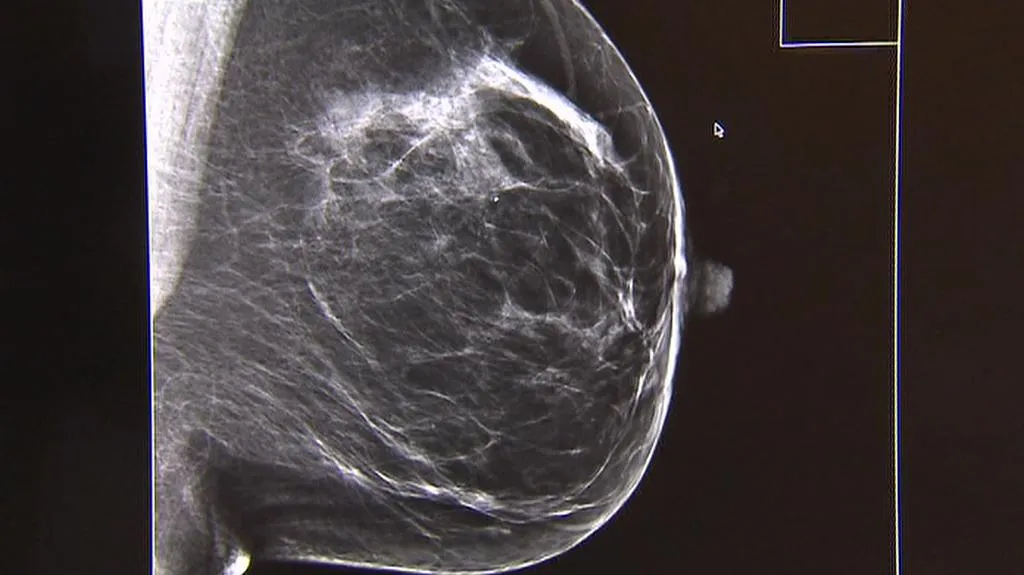

U rakoviny prsu ale významnou roli hraje věk. Ze zmiňovaných šesti tisíc nových pacientek za rok je zhruba jen stovka mladší pětatřiceti let, polovina je v rozmezí 50 až 70 let. Proto mají ženy starší 45 let mamografické vyšetření každé dva roky zdarma. Pokud chtějí screening častěji, musí si za něj stejně jako mladší ženy zaplatit, a to asi 500 až 700 korun.

V Česku je v současnosti sedm desítek mamografických center. Právě díky včasnému vyšetření přežije dnes o třetinu vyšší počet pacientek než před deseti lety. Na mamograf ale chodí jen polovina českých žen. Jejich počet by mělo pomoci zvýšit adresné zvaní, podle návrhu ministerstva zdravotnictví by preventivní vyšetření měly každé dva roky připomínat pojišťovny.